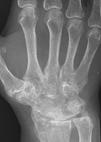

RA – Damaged fingers and wrist RA – Fused wrist bones

https://commons.wikimedia.org/wiki/File:Rheumatoide_Arthritis_der_Hand_65W_-_CR_ap_-_001.jpg

Description      Deutsch: Rheumatoide Arthritis der Hand. Zusätzlich Fingerfrakturen.

Date                 10 December 2020

Source              Own work

Author              Hellerhoff